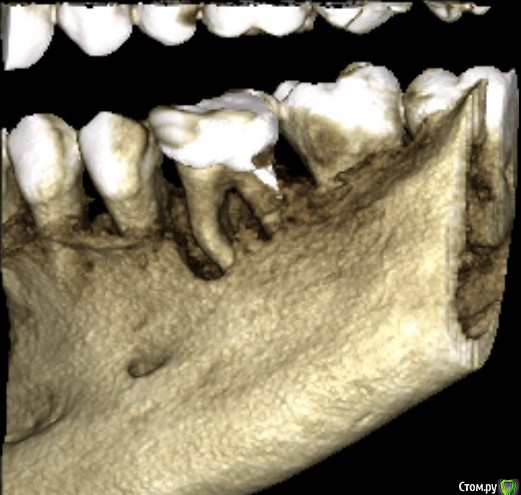

Constantine Опубликовано 28 января, 2019 Поделиться Опубликовано 28 января, 2019 (изменено) Здравствуйте, дамы и господа! В мае мне поставили циркониевую коронку на металлическую культевую вкладку (левая нижняя шестерка).Через месяц примерно образовался свищ под ней. Врач сказал полоскать содой - пройдет. Прошло. Еще через 2 месяца появилось ощущение, что коронка мешает немного. Пришел к врачу - он подпилил ее. Еще пару раз появлялись свищи. Говорил об этом врачу, он отвечал, что может быть перелом, но скорее всего все ок и нужно пополоскать содой. Несколько дней назад зуб под коронкой начал дико болеть. Пошел опять к врачу. Он сказал, что под корнем воспаление. Сделал надрез, почистил и отправил на КТ. Сделал КТ. Он говорит: "Хронический гранулирующий периодонтит. Есть два варианта: лоскутная операция с последующим плазмолифтингом или удаление. Но так как там полный трындец - лучше сразу удалять" Зуб до установки коронки не беспокоил (ничем кроме кариеса).Врач говорит, что проблема была скорее всего до установки коронки и он тут ни при чем.На вопрос, зачем же тогда ставили коронку, отвечает, что не видел ничего на снимках. Вопросов два:Как понять, виноват ли мой нынешний врач, ставивший коронку, или врач, который изначально пломбировал каналы? Что делать? Пробовать спасать зуб? Или уже позняк метаться и только рвать? На панорамном снимке - зуб до коронки, на КТ - то, что сейчас. Благодарю! Изменено 28 января, 2019 пользователем Constantine Ссылка на комментарий

___49___ Опубликовано 28 января, 2019 Поделиться Опубликовано 28 января, 2019 (изменено) Здравствуйте, На первый вопрос не отвечу , не эксперт, давать подобные заключения не могу - форум в принципе ориентирован на помощь в решении клинических вопросов . По поводу 2 го вопроса , скорее всего удаление ( скиньте срезы КТ , а не 3D виртуальную модель 36го зуба) . Изменено 28 января, 2019 пользователем ___49___ Ссылка на комментарий

Constantine Опубликовано 30 января, 2019 Автор Поделиться Опубликовано 30 января, 2019 (изменено) Здравствуйте, На первый вопрос не отвечу , не эксперт, давать подобные заключения не могу - форум в принципе ориентирован на помощь в решении клинических вопросов . По поводу 2 го вопроса , скорее всего удаление ( скиньте срезы КТ , а не 3D виртуальную модель 36го зуба) .Вот это? Изменено 30 января, 2019 пользователем Constantine Ссылка на комментарий

___49___ Опубликовано 30 января, 2019 Поделиться Опубликовано 30 января, 2019 Вот это?да - удаляйте зуб. 3 Ссылка на комментарий